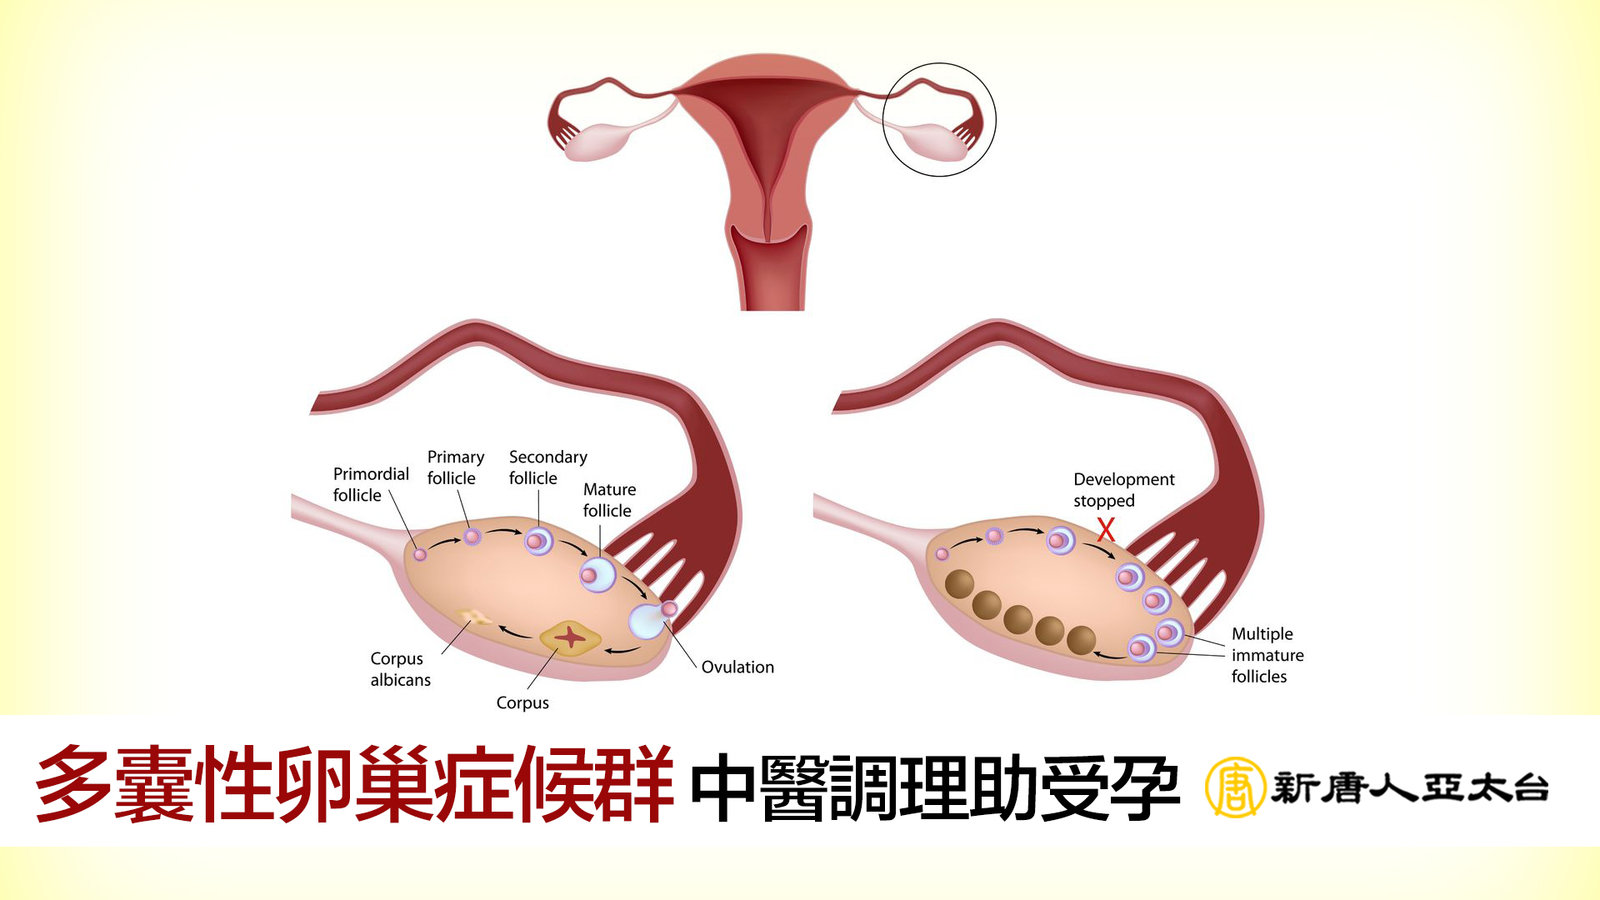

經期異常、突然變胖 小心多囊性卵巢症候群找上你|談古論今話中醫(339)

2017-02-10 17:46:05多囊性卵巢綜合症是一個內分泌紊亂的情形,這種症狀的女性都是有共同的一些問題,如月經不規則、不孕、肥胖、男性特徵有點明顯、流產等。 這一集我們邀請到全昌堂中醫診所院長徐慧茵中醫師來到現場來談這女性不少見的問題。

女性不孕症大元凶 多囊性卵巢症候群 中醫調理幫助好受孕 | 談古論今話中醫(448)

2019-09-02 11:09:31據報導有位39歲陳姓婦人經西醫婦產科診斷是「多囊性卵巢症候群(PCOS)」患者,不僅月經不規則,8年來無法受孕、體重狂增30多公斤,求醫無門後找中醫調理5個月,恢復正常,如今已懷孕8個月。甚麼是多囊性卵巢症候群、中醫如何調理呢?今天很高興邀請到中醫全國聯合會副秘書長彭溫雅醫師來到現場解說這現代很常見的婦科疾病。

女性不孕症大元凶 多囊性卵巢症候群 中醫調理幫助好受孕 | 談古論今話中醫(448)預告

2019-09-02 11:30:30據報導有位39歲陳姓婦人經西醫婦產科診斷是「多囊性卵巢症候群(PCOS)」患者,不僅月經不規則,8年來無法受孕、體重狂增30多公斤,求醫無門後找中醫調理5個月,恢復正常,如今已懷孕8個月。甚麼是多囊性卵巢症候群、中醫如何調理呢?今天很高興邀請到中醫全國聯合會副秘書長彭溫雅醫師來到現場解說這現代很常見的婦科疾病。

治多囊性卵巢症候群 中醫優勢最顯著|談古論今話中醫(339)預告

2017-02-03 22:30:19多囊性卵巢綜合症是一個內分泌紊亂的情形,這種症狀的女性都是有共同的一些問題,如月經不規則、不孕、肥胖、男性特徵有點明顯、流產等。 這一集我們邀請到全昌堂中醫診所院長徐慧茵中醫師來到現場來談這女性不少見的問題。

經期異常、突然變胖 小心多囊性卵巢症候群找上你|談古論今話中醫(339)電視版

2017-02-03 22:30:52多囊性卵巢綜合症是一個內分泌紊亂的情形,這種症狀的女性都是有共同的一些問題,如月經不規則、不孕、肥胖、男性特徵有點明顯、流產等。 這一集我們邀請到全昌堂中醫診所院長徐慧茵中醫師來到現場來談這女性不少見的問題。